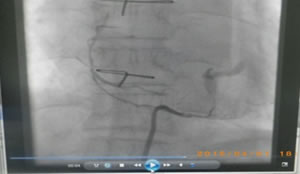

下の写真は、冠動脈バイパス術後の造影です。すでに手術から数日経った退院前の造影検査です。我々心臓外科医にとっては、循環器内科医師の先生からの「試験」を受けているようなモノです。ここで良い評価が得られないと、内科からの手術適用患者の紹介が途絶えることになります。

図6:右胃大望動脈をグラフトとして右冠動脈に吻合した例

図7:一本の大伏在静脈をグラフトとして使い、3箇所に分けて吻合した例

この術式は「sequential bypass (シークエンシャルバイパス)」と言います。

非常に難度が高いです。